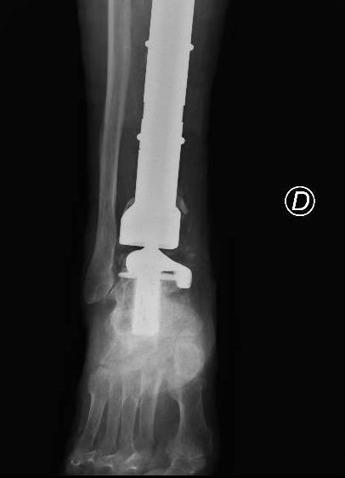

(Adnkronos) – Una protesi di caviglia costruita su misura salva la gamba bionica di Mario, paziente 80enne protagonista di un raro intervento eseguito al Policlinico Gemelli di Roma e definito "unico nel suo genere". Una travagliata storia a lieto fine cominciata una decina di anni fa quando Mario, ex coltivatore diretto, fu colpito da un cancro alle ossa. Ancora oggi, nonostante gli anni e gli acciacchi, Mario continua a occuparsi del suo orticello in una campagna in provincia di Viterbo. Ma sono tanti gli ostacoli che l'anziano ha dovuto superare e che sono iniziati 10 anni fa con un dolore sempre più forte e insistente alla gamba destra. Dopo una serie di esami, l'ortopedico consultato da Mario gli ha comunicato che quei fastidi erano causati da un tumore osseo raro (un adamantinoma) a carico della tibia. Alla diagnosi è seguita la resezione del tumore con impianto di una mega-protesi di tibia prossimale, cioè nell'area vicino al ginocchio. Dopo circa un anno dall'intervento, però, una grave infezione della protesi impiantata ha costretto Mario a subire una serie di complessi interventi chirurgici che si sono conclusi con l'impianto di una protesi totale di gamba e di caviglia in titanio, rivestita in argento per evitare nuove infezioni. Una gamba bionica. Ma ancora non era finita. A distanza di 6 anni, Mario torna dagli ortopedici del Gemelli per un dolore alla caviglia. Gli esami rilevano la rottura di una vite della protesi, a livello della caviglia. E' necessario sostituire il pezzo, ma l'unico modo per farlo – decretano gli specialisti – è facendo confezionare una protesi 'custom-made', disegnata e realizzata su misura. Gli ortopedici del Gemelli inviano perciò la Tac di Mario all'Implantcast, una ditta specializzata di Buxtehude, cittadina a sud ovest di Amburgo, in Germania. Basandosi sulla ricostruzione tridimensionale della caviglia bionica di Mario, i bioingegneri realizzano un calco della protesi custom-made con una stampante 3D, sul quale viene realizzata la protesi in titanio per l'impianto definitivo. Ed ecco l'intervento effettuato da Carlo Perisano, professore aggregato dell'Università Cattolica del Sacro Cuore e dirigente medico presso la Uoc di Ortopedia e Traumatologia della Fondazione Policlinico Gemelli, diretta da Giulio Maccauro. L'operazione dà i suoi frutti: "A distanza di appena qualche giorno dall'intervento, Mario sta di nuovo in piedi sulla sua gamba bionica arricchita di quest'ultimo gioiello tecnologico", riferiscono dall'Irccs capitolino. "Il paziente – afferma Perisano – era stato sottoposto negli anni a diversi interventi chirurgici per il trattamento di un tumore osseo della tibia e delle successive complicanze che avevano compromesso anche le articolazioni del ginocchio e della caviglia. Nel 2019 è stato sottoposto a posizionamento di mega-protesi custom-made personalizzata di tibia totale ginocchio e caviglia, scongiurando così il rischio di una chirurgia demolitiva, ovvero dell'amputazione dell'arto, garantendo al paziente il ritorno alle normali attività quotidiane". "Le protesi personalizzate (o custom-made) – illustra lo specialista – rappresentano un'innovazione significativa in ambito ortopedico. Si tratta tuttavia di impianti costosi, proprio perché realizzati su misura, che vengono per questo riservati a casi particolari e selezionati. L'impiego di tali protesi ci consente di personalizzare l'intervento sulle specifiche esigenze del paziente, garantendo un'accurata riproduzione anatomica ed un elevato grado di recupero funzionale. Nel caso specifico, la realizzazione di una componente astragalica su misura ci ha consentito di revisionare l'attuale protesi di caviglia e ha permesso al paziente un precoce ritorno ad un livello funzionale normale". E dal Gemelli rimarcano che "la revisione con una protesi di caviglia custom made di una protesi totale di caviglia e tibia è un intervento finora mai descritto in letteratura". "L'obiettivo di questi interventi di alta specializzazione – spiega ancora Perisano – è quello di minimizzare le complicanze, scongiurare il ricorso a chirurgie demolitive e consentire al paziente di proseguire la sua normale vita quotidiana. Le protesi personalizzate sono progettate su misura per il singolo paziente, tenendo conto delle peculiari caratteristiche anatomiche e della tipologia di trattamento. Nel caso specifico del signor Mario abbiamo fatto realizzare una protesi su misura per la sua caviglia, un'articolazione per la quale il ricorso all'uso di protesi customizzate è molto meno frequente rispetto ad articolazioni come anca, ginocchio e spalla e non scevro da difficoltà tecniche ed anatomiche". Nei mesi precedenti all'intervento chirurgico è stato elaborato un protocollo di pianificazione chirurgica, con un prototipo della componente astragalica e tibiale, che comprendeva dettagliate indicazioni relative ai tagli di resezione ossea, alle dimensioni della componente e a tutti gli step intra-operatori, riporta una nota. Successivamente, previa accurata valutazione del progetto e dopo ulteriori modifiche, è stata realizzata la componente protesica definitiva. "Si tratta di interventi di estrema precisione – commenta Maccauro, ordinario di Ortopedia dell'Università Cattolica – Grazie ad un'accurata pianificazione pre-operatoria e allo strumentario dedicato ed estremamente sofisticato necessario per il confezionamento di queste protesi speciali (maschere di taglio, guide per posizionare le componenti protesiche e la protesi custom made stessa), ci è possibile effettuare interventi molto precisi che riducono gli errori intraoperatori e guidano l'operatore nei processi decisionali e nell'atto chirurgico impensabili in passato". —salutewebinfo@adnkronos.com (Web Info)